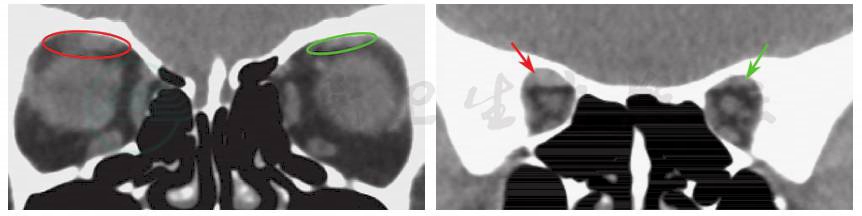

分析患者病情:患者复视发生于白内障术后一周,此后逐渐加重,术中麻醉方式为表面麻醉联合球后麻醉。于是先行眼眶CT排查是否存在不自知的外伤引起的眼眶骨折。眼眶CT示:近总腱环处上直肌增粗,周围脂肪间隙边界模糊,眶骨连续性完整;随后行眼眶核磁共振检查,核磁影像显示:近总腱环处上直肌肌腹增粗(图2,图3)。考虑到手术前无斜视,手术中局麻采用球后注射,术后早期出现复视,随时间延长斜视逐渐加重,并结合典型近总腱环周围肌肉增粗的影像学表现,诊断为麻醉相关性斜视。

图3 眼眶CT检查

环形标记及箭头所示为两侧上直肌肌腹、肌肉周围间隙对比。